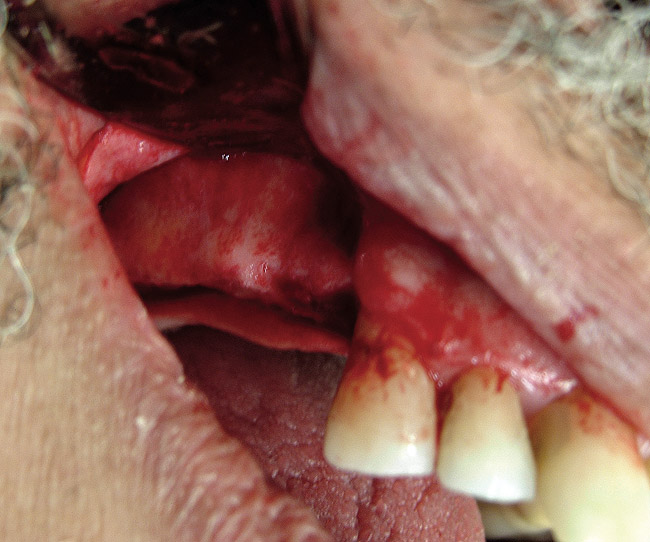

The lateral approach is also used for sinus floor elevation. It is indicated when there is reduced residual bone height, which does not allow standard implant placement or placement of implants in combination with minor sinus floor elevation using the osteotome technique (Figure 1, Figure 2 and Figure 3). Contraindications are excessive interarch distance due to unfavorable crown-to-root ratio, acute or chronic unresolved sinusitis, current sinus pathology (eg, cysts or tumors), lodged root tips in the sinus, history of heavy smoking, a systemic compromise, and psychological problems.

Figure  1  Elevation of the flap.

Figure 1